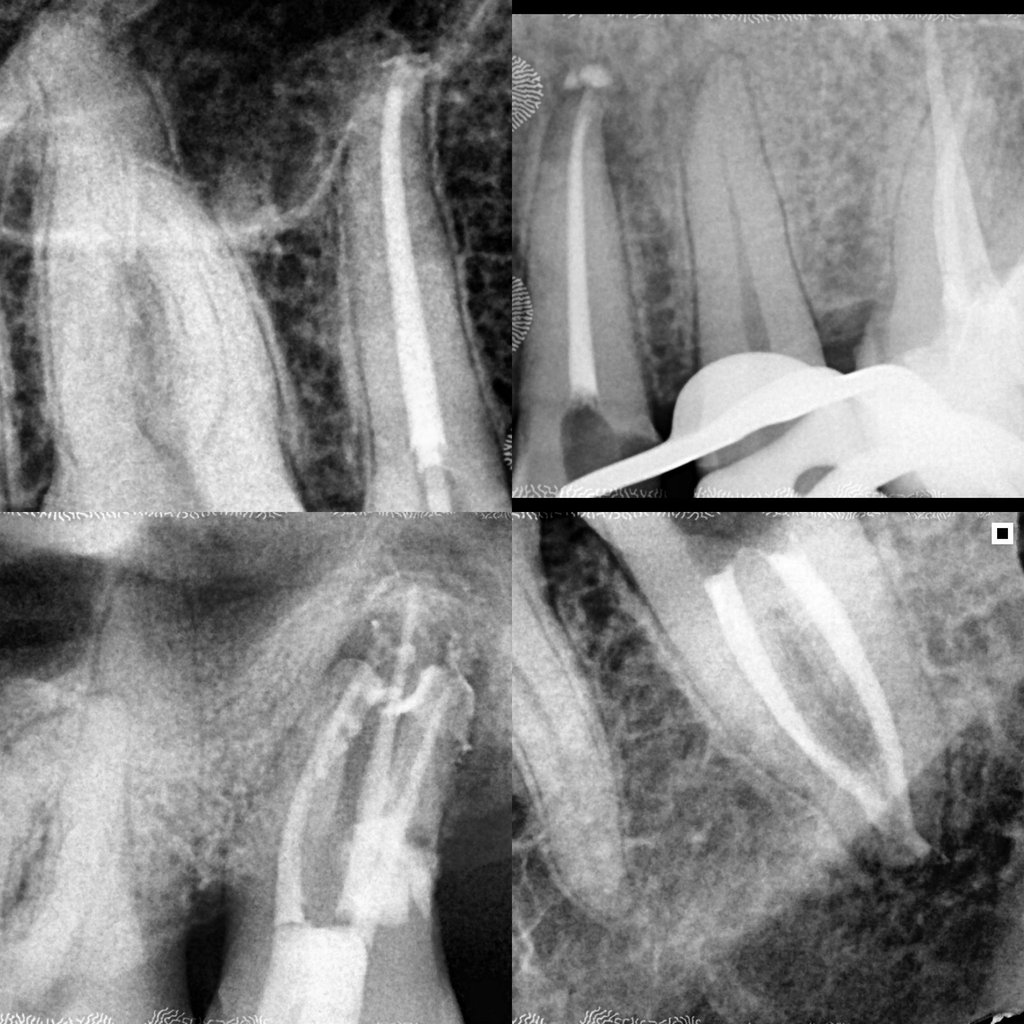

Em alguns casos, a necessidade de tratamento de canal é identificada em exames radiográficos, mesmo antes de o paciente sentir dor.

As radiografias periódicas podem revelar lesões na ponta da raiz, indicando um foco de infecção que precisa ser tratado.

Nesses casos, apenas o tratamento endodôntico é capaz de eliminar o problema e restaurar a saúde do dente.

Galeria

Na odontologia, cada sorriso é único e o resultado final depende de fatores biológicos individuais. Imagens clínicas não constituem promessa de resultado. Planejamento técnico e diagnóstico são fundamentais para o sucesso do tratamento."